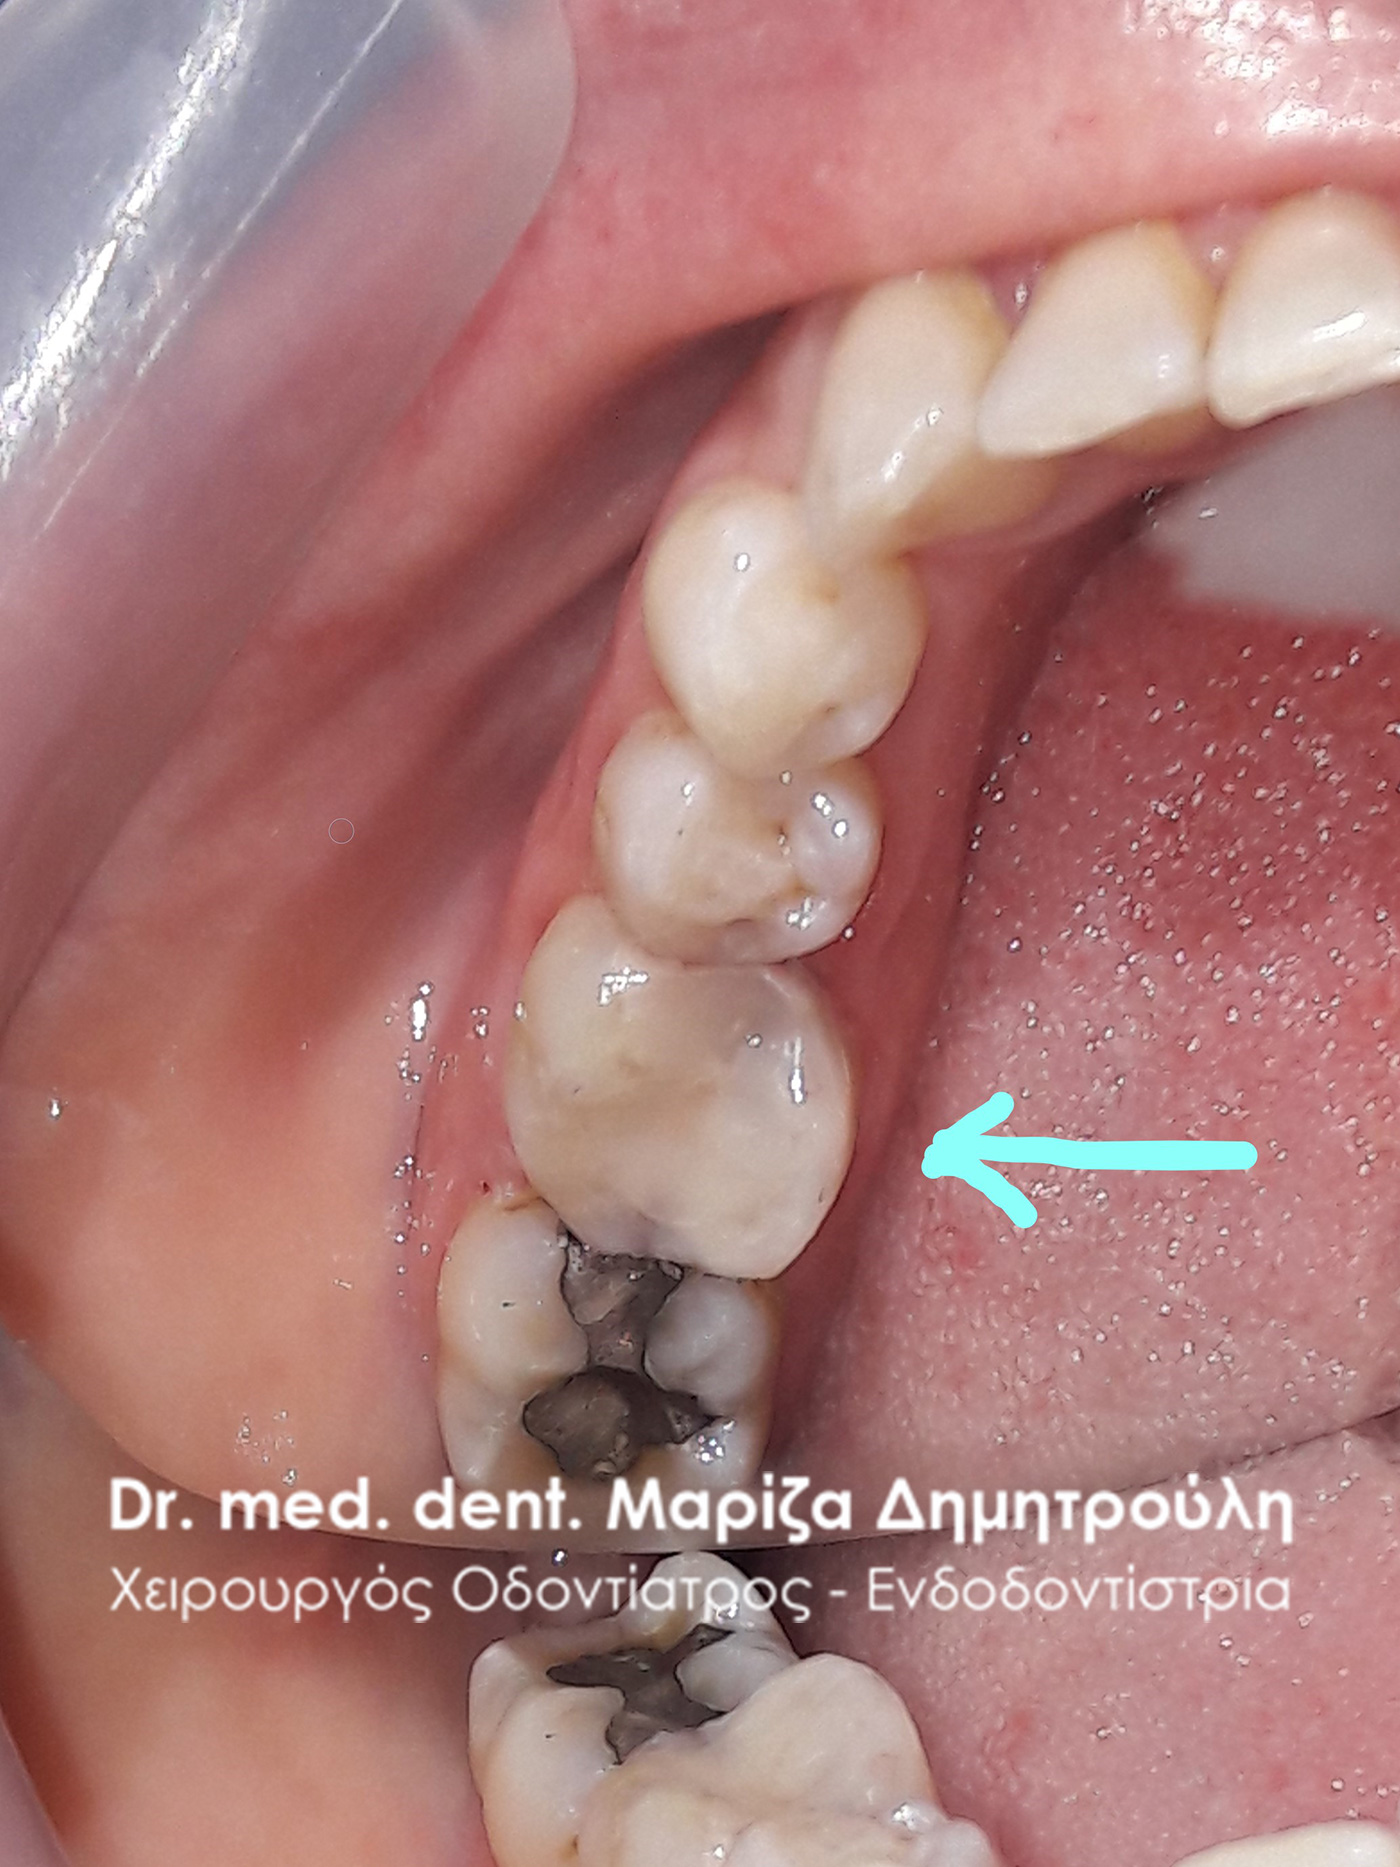

Removal of amalgam (silver) filling

BEFORE

BEFORE

AFTER

AFTER

AFTER